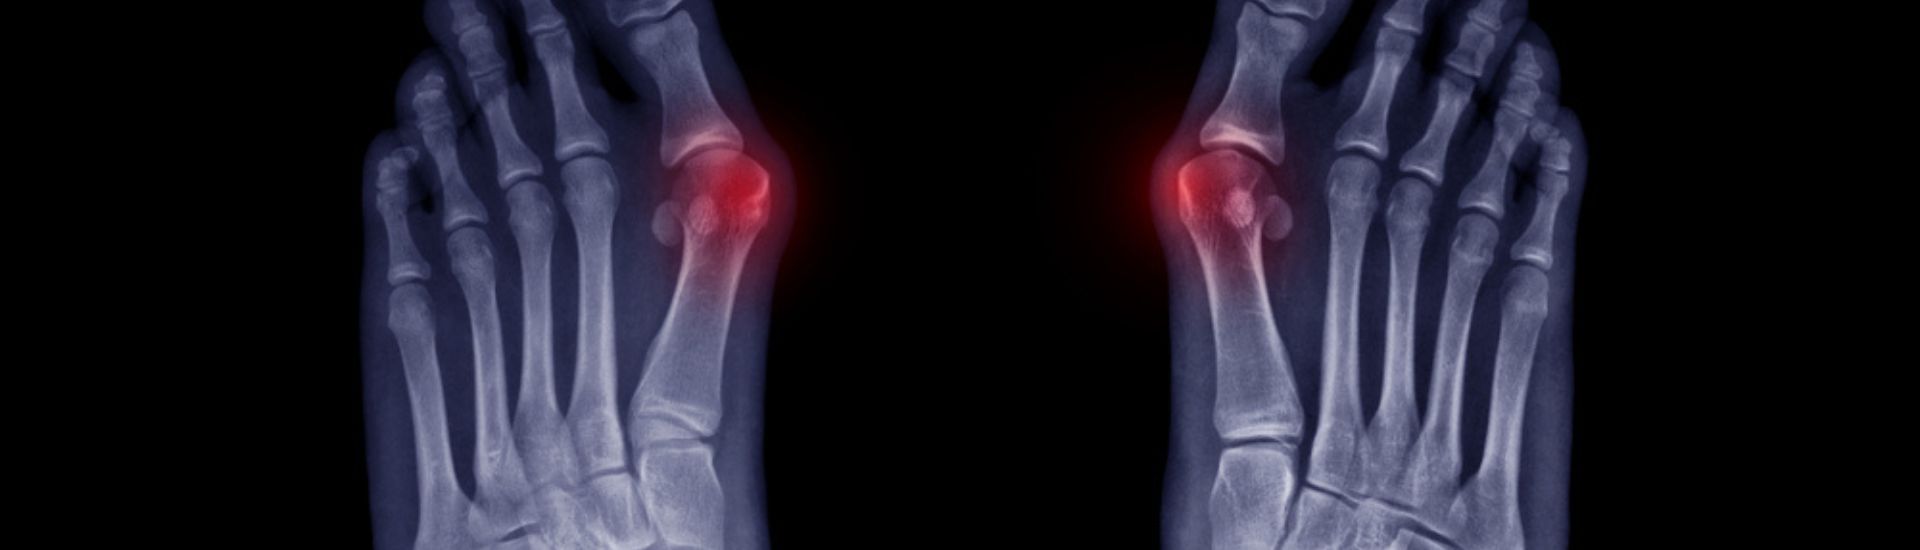

Ως βλαισός μέγας δάκτυλος ορίζεται η προς τα έξω απόκλιση του μεγάλου δακτύλου του ποδιού. Η εξόστωση που προκαλείται αποτελεί μια από τις συχνότερες παραμορφώσεις των κάτω άκρων και είναι γνωστή και ως «κότσι». Συχνά ο βλαισός μέγας δάκτυλος μπορεί να προκαλέσει επιπλέον παραμορφώσεις και συμπτώματα και στα υπόλοιπα δάκτυλα του ποδιού όπως εφίππευση του πρώτου δακτύλου με το δεύτερο.

Το βασικότερο σύμπτωμα του βλαισού μέγα δακτύλου είναι η εκδήλωση έντονου πόνου, εντοπισμένου στο σημείου του οστού που προεξέχει (εξόστωση), καθώς αυτό έρχεται σε επαφή με την εσωτερική επιφάνεια του παπουτσιού. Σταδιακά εκδηλώνεται τοπικά φλεγμονή με παρουσία οιδήματος, ερυθρότητας και σκληρίας. Με την επιδείνωση του πόνου υπάρχει δυσκολία κατά τη βάδιση ενώ ο ασθενής δυσκολεύεται να βρει υποδήματα που να μην του προκαλούν ενόχληση.

Με την πρόοδο της παραμόρφωσης εκδηλώνεται αρθρίτιδα στην 1η μεταταρσοφαλαγγική άρθρωση ενώ σε προχωρημένα περιστατικά υφίστανται παραμορφώσεις και τα άλλα δάκτυλα (π.χ. εφίππευση μεγάλου και δεύτερου δακτύλου).